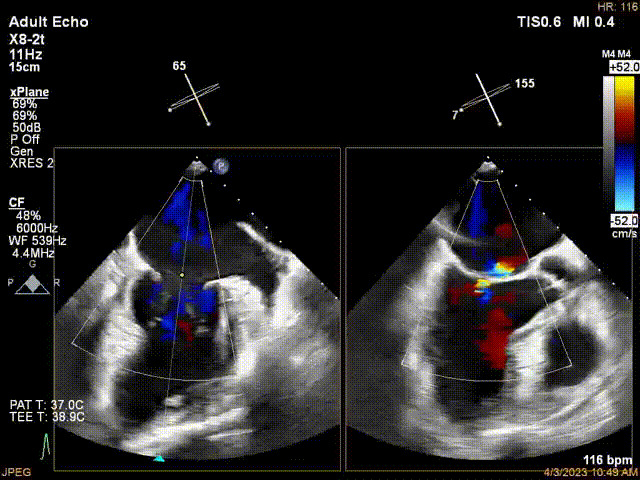

接受治療的是一例器質(zhì)性重度二尖瓣反流(DMR)患者,主訴“反復(fù)活動后胸悶,氣促3年余”。術(shù)前超聲顯示,雙房增大,二尖瓣脫垂伴重度反流,輕度三尖瓣反流,輕度肺高壓,升主動脈增寬。手術(shù)經(jīng)股靜脈-房間隔入路,采用全身麻醉插管,在TEE和DSA引導(dǎo)下完成房間隔穿刺。置入JensClip瓣膜夾系統(tǒng)后,在左房調(diào)整瓣膜夾的位置和軸向,后進(jìn)入左室,在TEE引導(dǎo)下捕捉二尖瓣前后瓣葉,并關(guān)閉瓣膜夾。經(jīng)TEE反復(fù)確認(rèn)手術(shù)效果后最終鎖定并釋放瓣膜夾。術(shù)后即刻超聲顯示瓣膜夾位置穩(wěn)定,功能良好,術(shù)前二尖瓣反流4+,術(shù)后0反流,肺靜脈逆流和左房壓都顯著好轉(zhuǎn),手術(shù)圓滿成功(以上數(shù)據(jù)都來源于醫(yī)院的臨床記錄)。術(shù)后患者狀態(tài)良好,目前已安排出院。

術(shù)前超聲提示二尖瓣重度反流